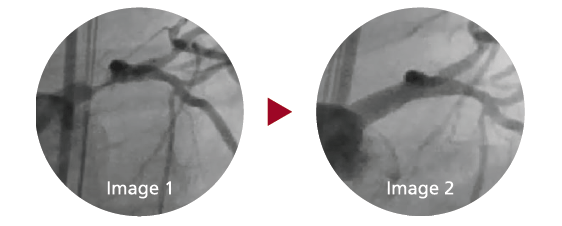

Image 1: 72 M hx of TIA presenting for concern of three hours of chest pain at rest, 7/10. Coronary angiogram reveals 90 percent left main stenosis and chronic total occlusion of the RCA.Patient was considered a high-risk candidate for CABG and decision for PCI with circulatory support, Impella 2.5 L made. Image 2: Result after a single drug-eluting stent in the left main 3.5 x 15 mm, post-dilated with a 4.5 mm balloon. The Impella was removed at the end of the procedure and the patient was discharged the next day in excellent condition.